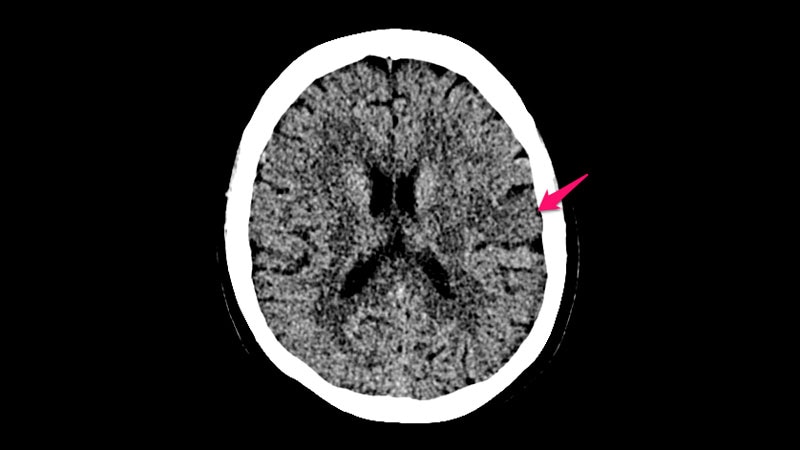

Tenecteplase Noninferior to Alteplase for Ischemic Stroke: TRACE-2The two drugs had similar efficacy and safety in ischemic stroke patients enrolled in TRACE-2, a phase 3 trial a Chinese population,

supporting a "worldwide" switch to tenecteplase, researchers say.